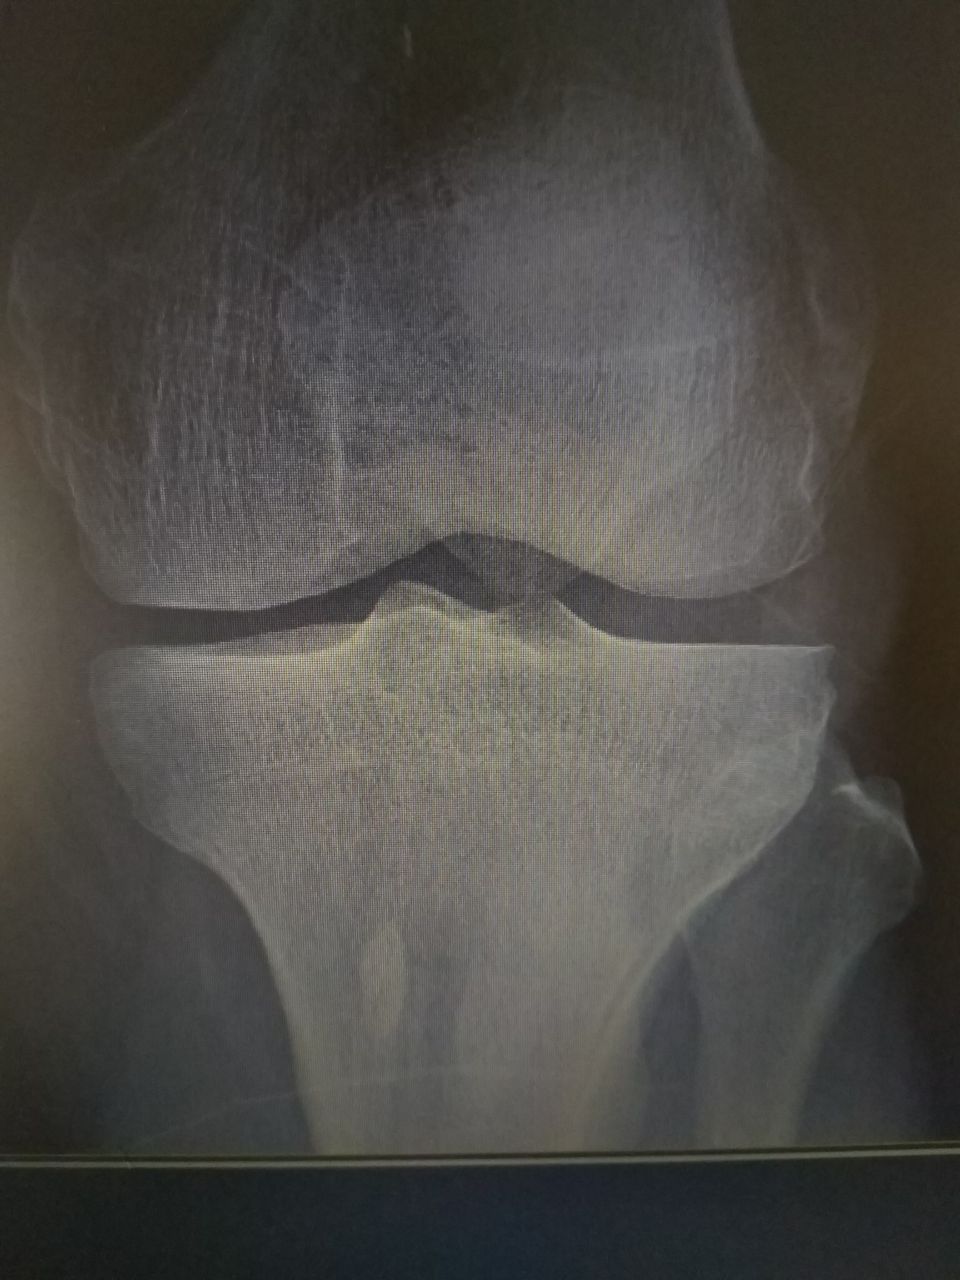

Отечность колена,боль

Возраст. Участок остеосклероза. Отправить на сцинтиграфию. Сустав вполне нормален.